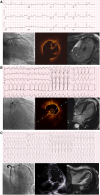

Aims: The diagnostic criteria for Type 2 myocardial infarction identify a heterogeneous group of patients with variable outcomes and no clear treatment implications. We aimed to determine the implications of a new clinical classification for myocardial infarction with more objective diagnostic criteria using cardiac imaging.

Methods and results: In a prospective cohort study, patients with Type 2 myocardial infarction underwent coronary angiography and cardiac magnetic resonance imaging or echocardiography. The new classification was applied to identify (i) spontaneous myocardial infarction due to acute coronary pathology, (ii) secondary myocardial infarction precipitated by acute illness in the presence of obstructive coronary artery disease, a new regional wall motion abnormality, or infarct-pattern scarring, and (iii) no myocardial infarction in the absence of obstructive disease or new myocardial abnormality. In 100 patients (65 years, 43% women) with Type 2 myocardial infarction, the new classification identified 25 and 31 patients with spontaneous and secondary myocardial infarction, respectively, and 44 without myocardial infarction. Compared with patients without myocardial infarction, those with secondary myocardial infarction were older, had more risk factors, and had higher troponin concentrations (P < 0.05 for all). During a median follow-up of 4.4 years, death, myocardial infarction, or heart failure hospitalization was more common in secondary myocardial infarction compared with those without myocardial infarction [55% (17/31) vs. 16% (7/44), P < 0.001].

Conclusion: A new clinical classification of myocardial infarction informed by cardiac imaging would reduce the diagnosis of myocardial infarction in acute illness and identify those patients at highest risk who are most likely to benefit from treatment.